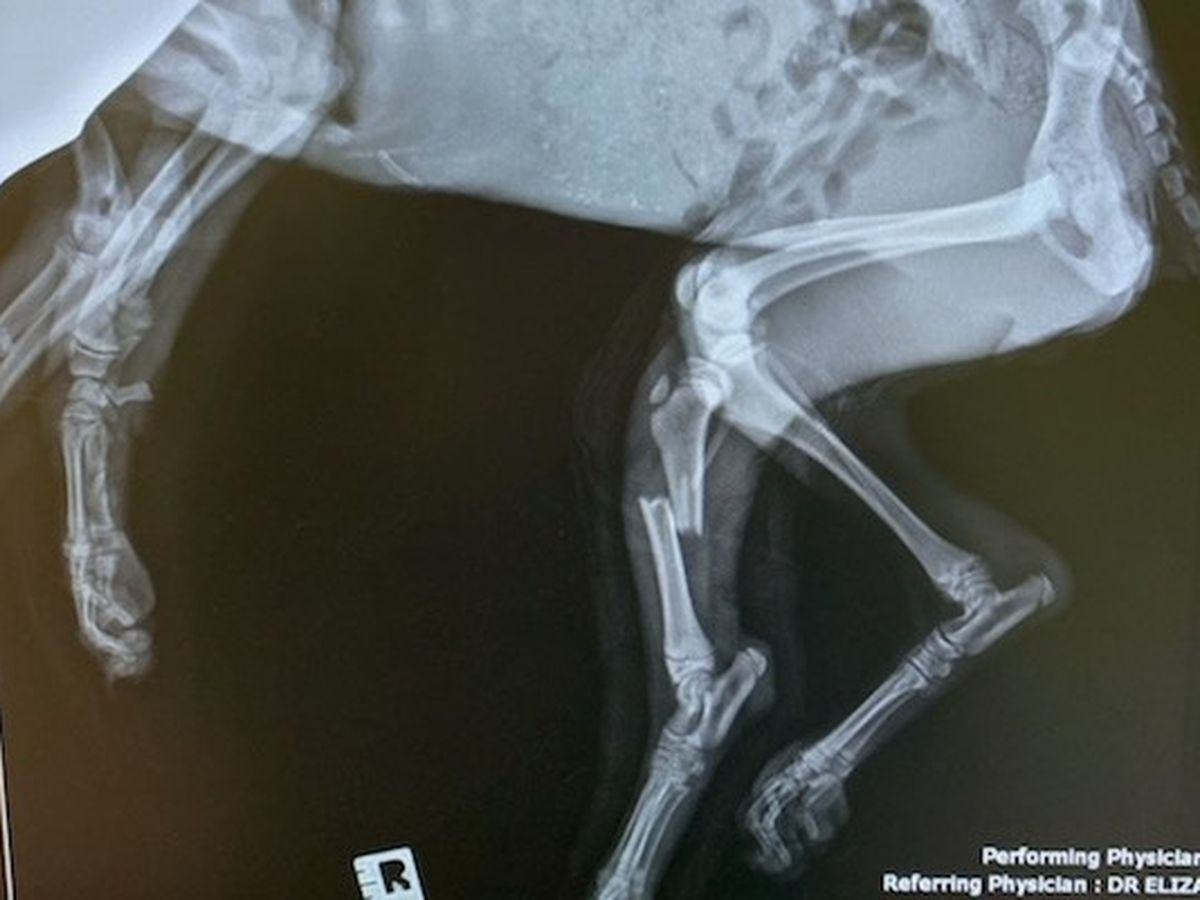

FMN immediately went to get her, taking her for X-rays where it was determined she has 3 fractured legs.